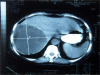

Results: Clinical manifestations of an abscess were identified in 75% of the patients. In the earlier cases of the study, the diagnosis was made from the clinical picture, laboratory studies, in combination with plain X-ray, hepatic scintigraphy, and in the later cases with US (ultrasonography), CT (computed tomography) or MRI (magnetic resonance imaging), and ERCP (endoscopic cholangiopangreatography). Abdominal and, rarely, thoracic and abdominal or thoracoabdominal incisions were used. Total cystopericystectomy in 8 patients and partial pericystectomy and proper drainage with one or two drainage tubes of the cystic cavity in the other 69 patients were carried out. Hospital stay was between 13 and 146 days with 5 re-operations. Two patients with grossly suppurated cysts and coexistent medical problems died. The disease recurred in five patients. CONCLUSIONS. We conclude that, under good perioperative antibiotic and metabolic coverage, the infected hydatid cysts have to be completely evacuated and properly drained. The application of "conservative" surgical procedures should be preferred. Further studies are needed to solve the clinical and therapeutic problems of this serious complication.